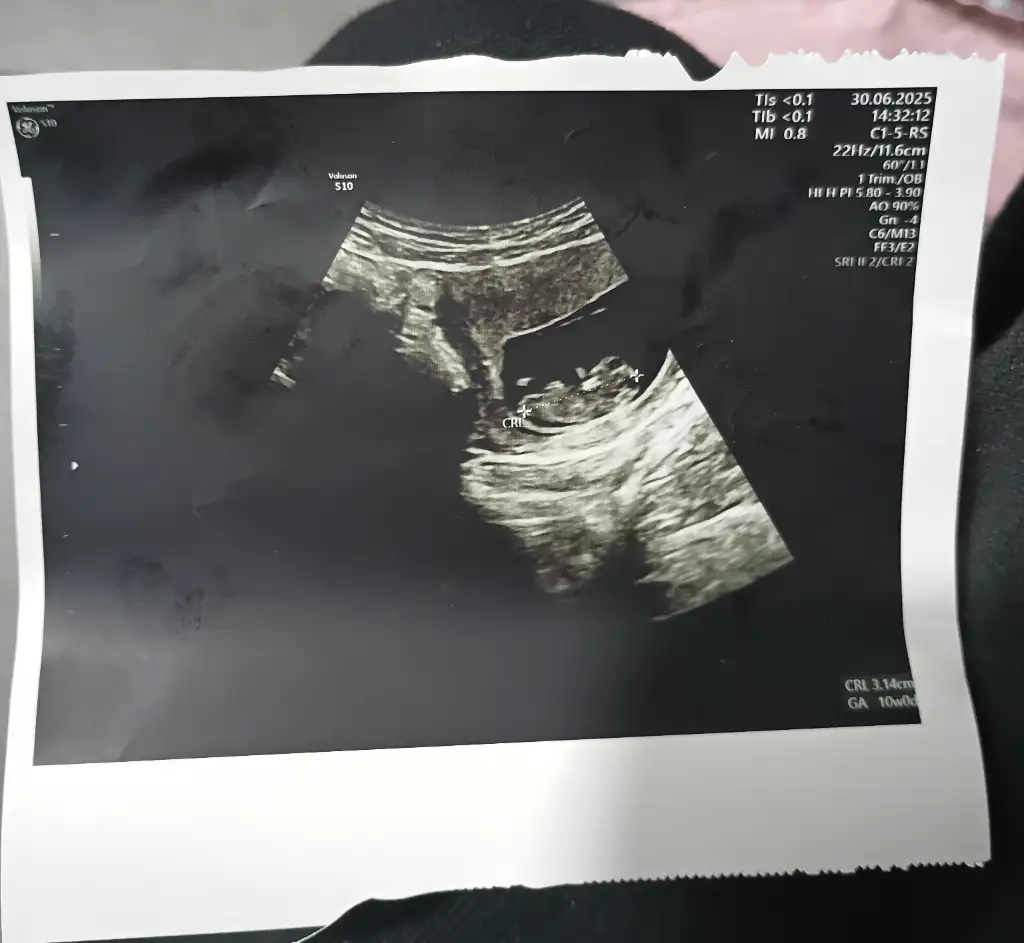

Bana da bakar mısınız lütfen biri 9 haftalık biri 6 haftalık karından ultrasonKese şekline göre erkek bence. Sağlıkla kucağınıza alın

Banada bakar mısnız lütfennnn çok merak ediyorum biri 9 haftalık biri 6 haftalık ultrason karından

link atar mısınYapay zekayada sordum 6 haftalık ve 8 haftalik iki resmede erkek dedi Rabbim nasip etsin inşallah

kese şekline göre cinsiyet diye sorSordum canım erken diyor